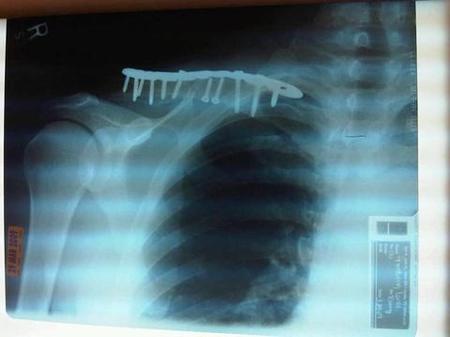

•鎖骨の下には重要な血管、神経が通っており

写真のように(!)骨を固定する際に、

それらを傷付ける可能性がある

さらに固定と解除で2回も手術しないといけません。